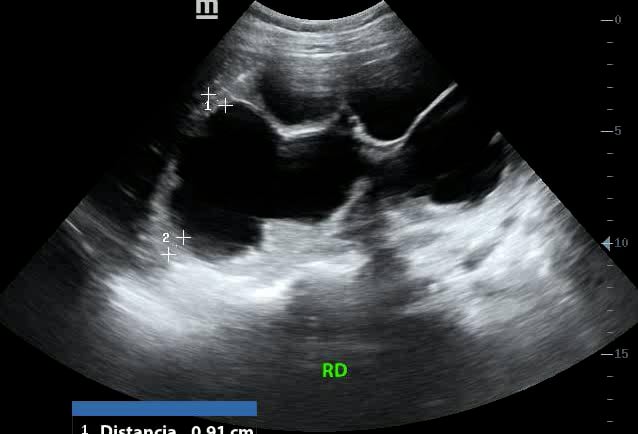

Hydronephrosis, in abdominal ultrasound, refers to the swelling of a kidney due to a buildup of urine. This occurs when there’s an obstruction in the urinary tract, preventing proper drainage. Common causes include kidney stones, tumors, or strictures, leading to dilation of the renal pelvis and calyces. Early detection via abdominal ultrasound is crucial to prevent irreversible kidney damage, as it provides non-invasive visualization of the urinary system and identifies the level of obstruction.

Medical ultrasound is essential for diagnosing hydronephrosis, offering real-time imaging that helps differentiate between various etiologies. Sonographers can assess the severity of kidney swelling, monitor progression, and guide interventions like stent placement. For accurate abdominal imaging, identifying hydronephrosis is key for timely management and preserving renal function, making it a critical aspect of diagnostic sonography.